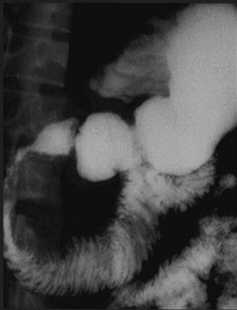

- Kontrastlı KT və ya MRT standart müayinədir, şişi və yayılma dərəcəsini müəyyənləşdirilməsində önəmlidir.

- Görüntüləmdə: erkən arterial fazada contrast tutan və venoz fazada yuyulan, MRT-də hipointens, ətraf toxumalara invaziv, böyüməyə meylli, baş nahiyyəsində yerləşərək xoledoxu və pankreatik axacağı genişləndirən (“iki axacaq simptomu”) törəmə